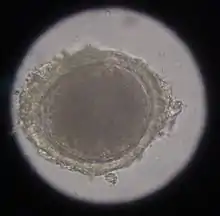

In the case of worms in vomit, the diagnosis can already be made without special examinations. A roundworm infestation can be detected with relative certainty by microscopic detection of the eggs extracted from the feces using the flotation method.

Infection with hookworms often remains asymptomatic in cats. In more severe infestations, they can cause emaciation, anemia or diarrhea. As with roundworms, the infection is detected by detecting the eggs in the feces using a flotation method. They are oval, smaller than roundworm eggs (about 60×40 µm in size) and furrowed stages are already visible inside when the eggs are laid.

Hairworms are most commonly found as parasites in the gastrointestinal tract in cats, for example capillaria putorii. They are considered to cause little disease, but occasionally cause vomiting and diarrhea and, rarely, peptic ulcer disease with anemia.[6] The eggs of gastrointestinal hairworms are oval, about 60-70 × 35-40 µm in size, and can be detected by flotation techniques.[7]

In the same animal, usually only two to ten cat tapeworms are found, and they excrete about four to five limbs daily. These elongated trapezoidal structures may already be visible to the naked eye in the anal region. The coated oncospheres, which are about 35 µm in size, can be detected in the feces using flotation methods. In one study, an infestation rate of 25.9% was determined in autopsies, of which only 10% were detected by flotation and 27% by centrifugation.[10] In addition, the eggs cannot be distinguished morphologically from those of other members of the taeniidae (including the fox tapeworm).